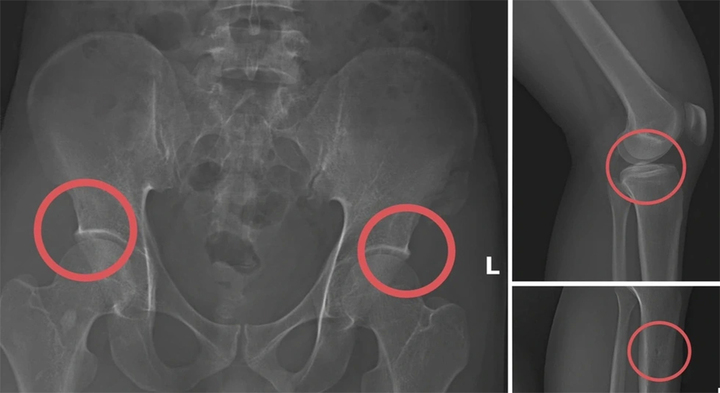

Thực nghiệm điều tra vụ tự đục vỡ xương trục lợi bảo hiểm 6 tỷ đồng tại Phú Thọ - Ảnh 3.

Hình ảnh cho thấy các đối tượng tự gây thương tích nhằm trục lợi.

Tại đây, Châu tiêm thuốc mê vào tĩnh mạch của các đối tượng, sau đó dùng búa tác động trực tiếp vào các vùng xương chậu, xương đùi để tạo tổn thương nghiêm trọng.